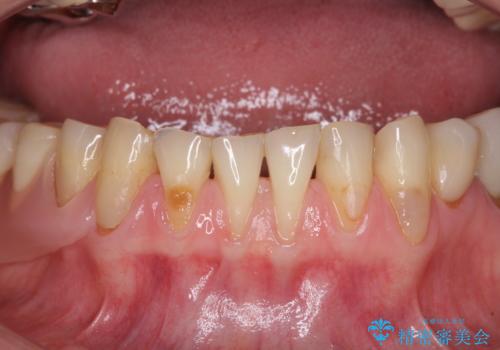

前歯の歯肉退縮 歯肉移植による根面被覆

担当医 藤巻太一朗